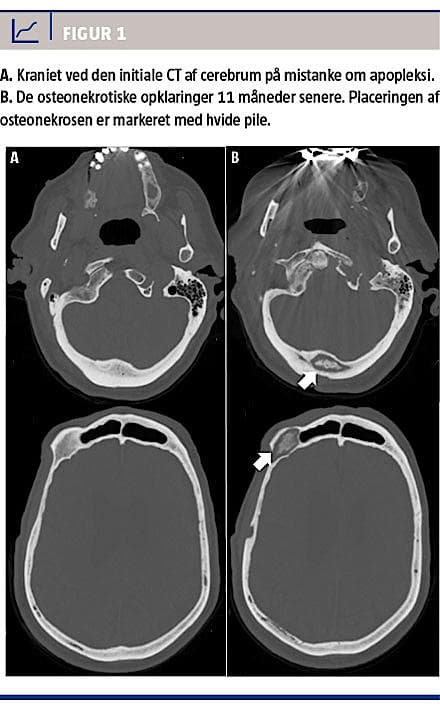

I efterforløbet dannedes der fistler omkring cikatricen og over højre øje, hvorfra der aldrig var biopteret. Patienten havde da haft generende kraniesmerter i 11 måneder og undervejs fået foretaget tre MR-skanninger af cerebrum, to CT’er af cerebrum, en knoglescintigrafi og en PET-CT, som alle viste progredierende osteolytisk osteonekrose flere steder i kraniet (Figur 1). Ydermere var der foretaget flere CT’er af thorax-abdomen og UL-skanning af abdomen, hvor man fandt normale forhold fraset den kendte coloncancer. Mistanken om metastasering fra hhv. prostatacanceren og coloncanceren ansås for at være afkræftet i kraft af de tre negative patologisvar. Behandlingsmæssigt valgte man en afventende strategi, da patientens gener kom fra fistelsekretionen. Hovedpinen var nu sparsom og aftagende, og der var en fortsat bedring i almentilstanden. Andre differentialdiagnoser var derfor aktuelle, herunder specielt prednisolonudløst aseptisk osteonekrose, overset malignitet, morbus Paget, aseptisk osteomyelitis og mange flere.

Der findes mange differentialdiagnoser til osteonekrose (Tabel 1). Højdosissteroidbehandling, som patienten fik i forbindelse med mistanken om arteritis temporale er kendt for at kunne medføre avaskulær osteonekrose [1]. Lidelsen findes ofte i de vægtbærende knogler med præference for specielt hofteleddet, hvorfor en fremkomst i kraniet ville være sjælden [2]. Steroidinduceret osteonekrose fører til trabekulær kollaps af den spongiøse knoglestruktur [3]. Dette stemmer ikke overens med patientens kranieopklaringer, da disse var af ekspansiv karakter (Figur 1).